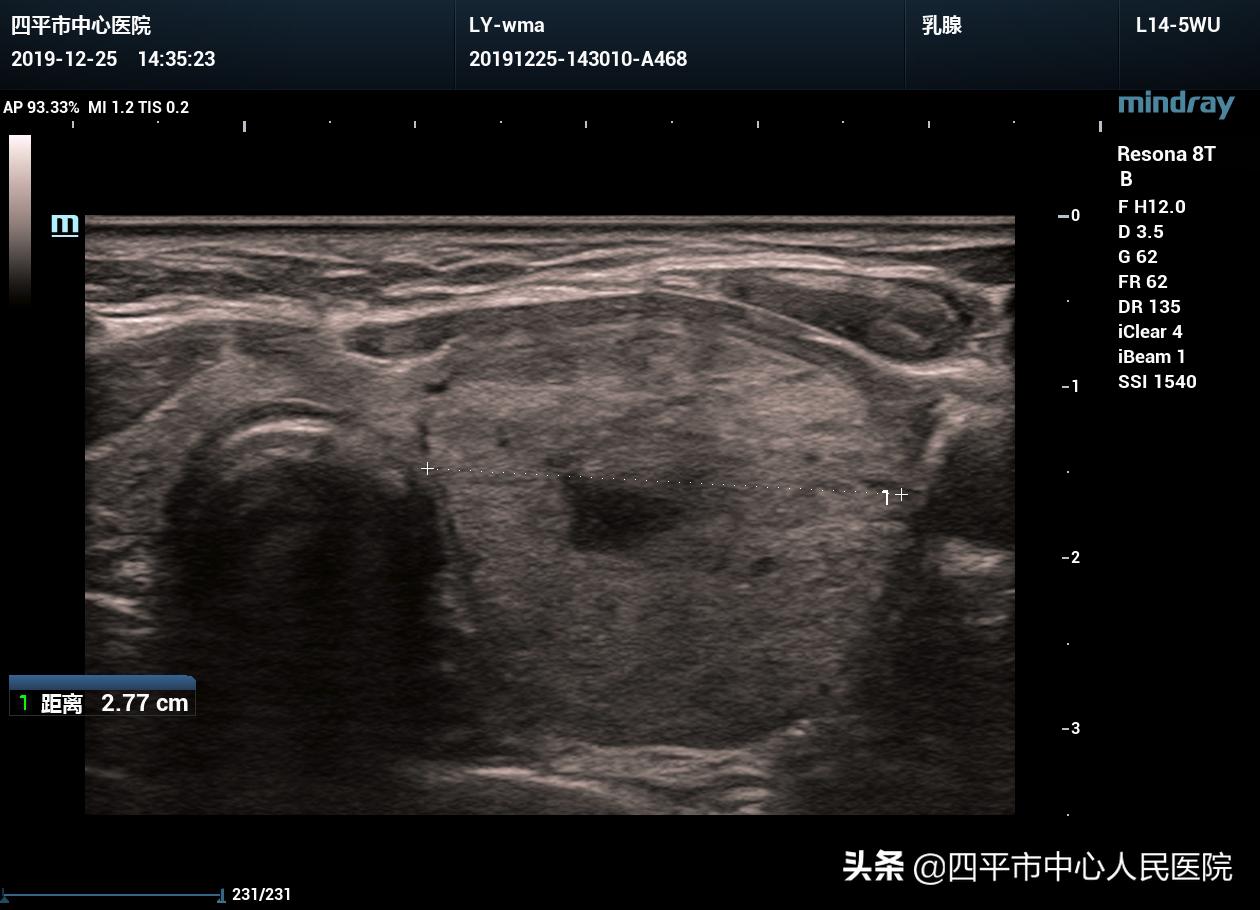

3、檢查:可能需要進行血常規、尿常規、甲狀腺功能檢查、甲狀腺超聲等檢查,以明確結節的性質和大小。